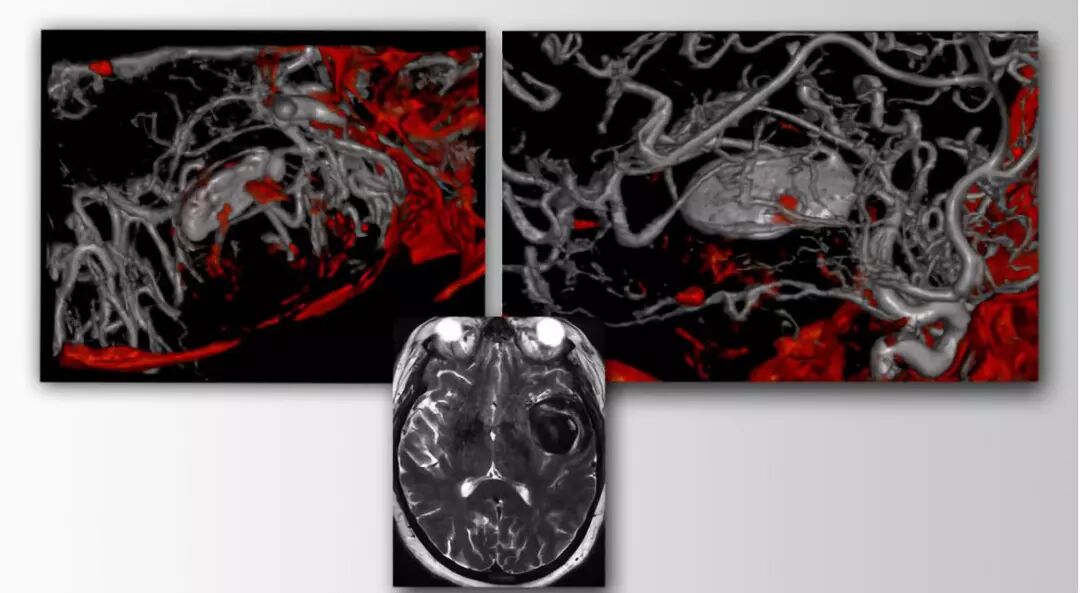

术前应当细致评估,包括CTA。应当注意MCA三分叉的情况。术前必须行血管造影以明确瘤颈形态,隐藏于瘤囊后的主干血管部位和颞浅动脉是否适合作血运重建。应当评估侧支循环情况。二分叉处M2主干流出道狭窄并不罕见;如果行显微夹闭,术者在二分叉后方近端应留出适当空间,以避免M2狭窄。

在瘤颈或瘤顶存在钙化斑提示需做血运重建的准备。影像学上瘤顶的轻微钙化常伴有瘤颈的钙化。瘤内血栓在瘤腔的部位很重要。为减少临时阻断时间,笔者在血管开放状态下切开瘤囊并切除血栓直到出血。此时以临时夹孤立动脉瘤。此时需对瘤顶切口作精确设计。

血管动脉硬化存在提示侧支循环差、缺血风险大,即使是在爆发抑制条件下中等阻断时间(10-15分钟)。在这种情况下,应考虑事先作搭桥准备。

图1. 一个伴部分血栓形成的巨大MCA动脉瘤(M2近段),瘤壁有钙化斑。先于远端行血运重建,再于二分叉后行近端阻断,使动脉瘤内形成血栓。